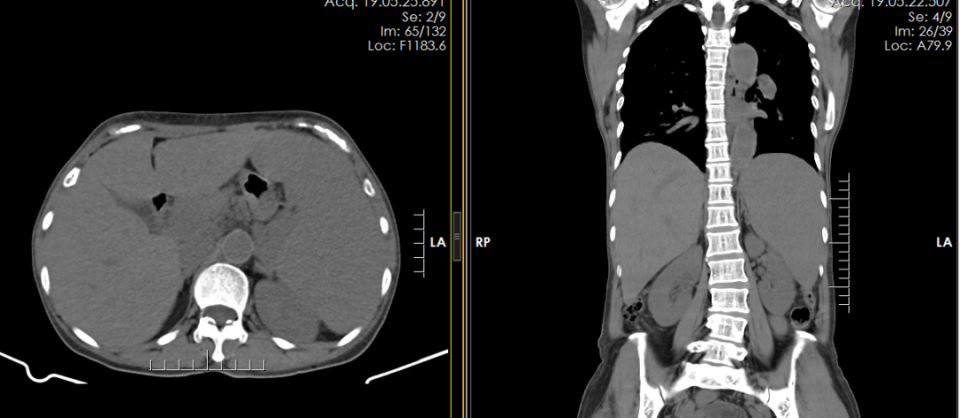

CT提示脾脏明显增大,约为正常的3倍。